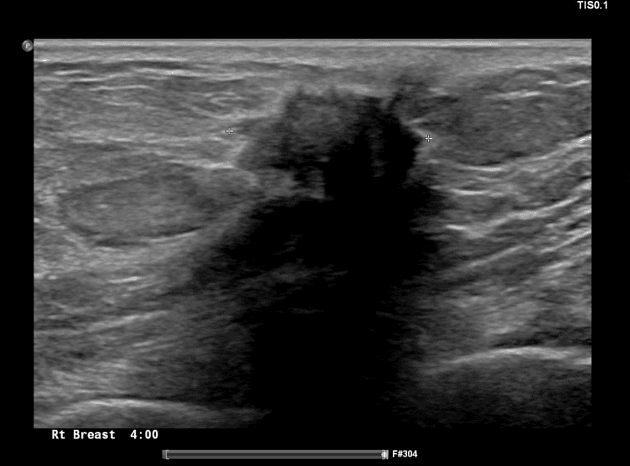

- Vú bên trái xuất hiện một tổn thương dạng đặc (solid), giảm âm (hypoechoic) đơn độc với giới hạn không rõ (ill-defined), bờ dạng gai (spiculated margins), được xác định ở tứ phân vị dưới ngoài tại vị trí 5 giờ sau quầng vú (retro-areolar).

- Khối choán chỗ (mass) có kích thước khoảng 16 x 15 mm, nằm cách núm vú 21 mm và cách bề mặt da 7,3 mm.

- Tổn thương có trục đứng (taller-than-wide) (không song song - non-parallel), đường bờ không rõ (indistinct borders), có bóng lưng phía sau (posterior acoustic shadowing) và tăng tưới máu (vascularity) ngoại vi nhẹ trên hình ảnh Doppler.

- Có các vi vôi hóa (microcalcifications) rải rác bên trong.

Kết luận: BI-RADS vú trái phân loại 5 — các phát hiện nghi ngờ ác tính cao.